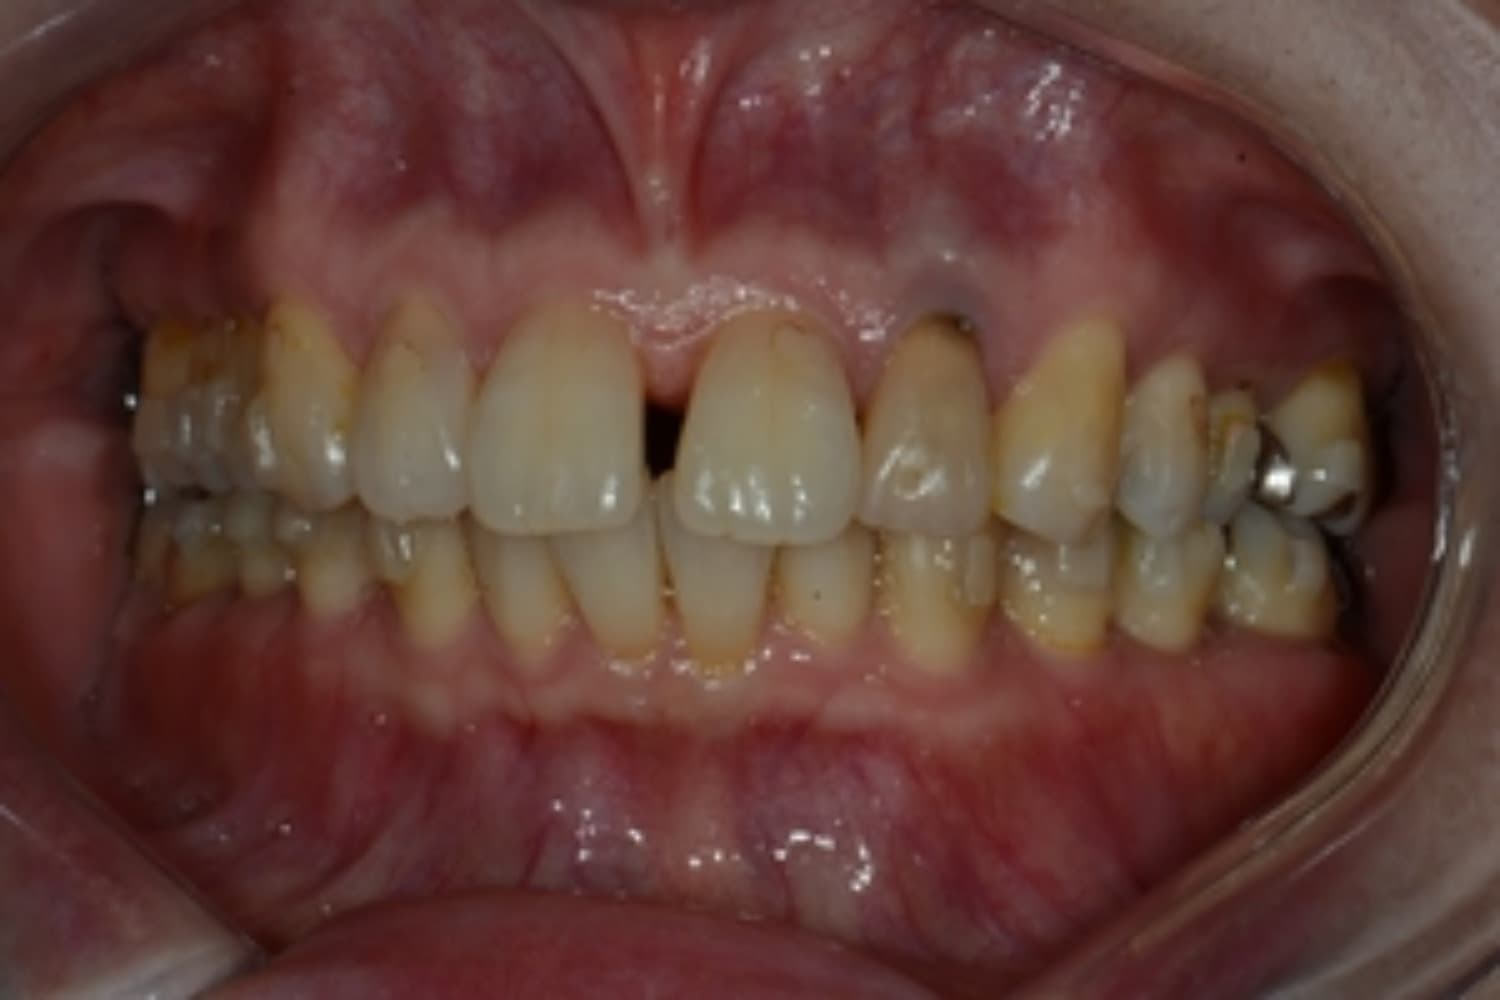

上顎前歯2本欠損症例(2)

Before

After

保存が困難な状態であったため抜歯をおこない、その後インプラントを2本埋入しました。

年齢

67歳

性別

女性

主訴

右上前歯は以前に別の医院で治療中でしたが中断されたため、当院へご相談くださいました。

治療期間

10ヵ月

費用

120万円

副作用・リスク

インプラント治療は外科的な処置を伴い、多少の腫れや痛みが出ることがあります。 多くの場合は鎮痛薬で和らげることができます。